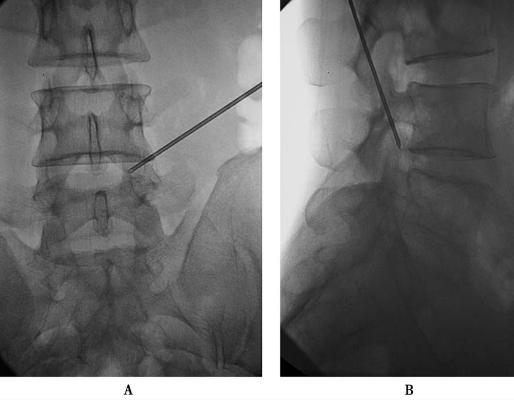

上关节突尖的腹侧(图12):调整勺状针的勺状面向腹侧,稍加大穿刺角度,使针尖略向腹侧进针,滑过上关节突尖部进入椎间孔,注入局麻药3ml。

图12勺状针针尖抵达上关节突尖的腹侧A.前后位透视;B.侧位透视